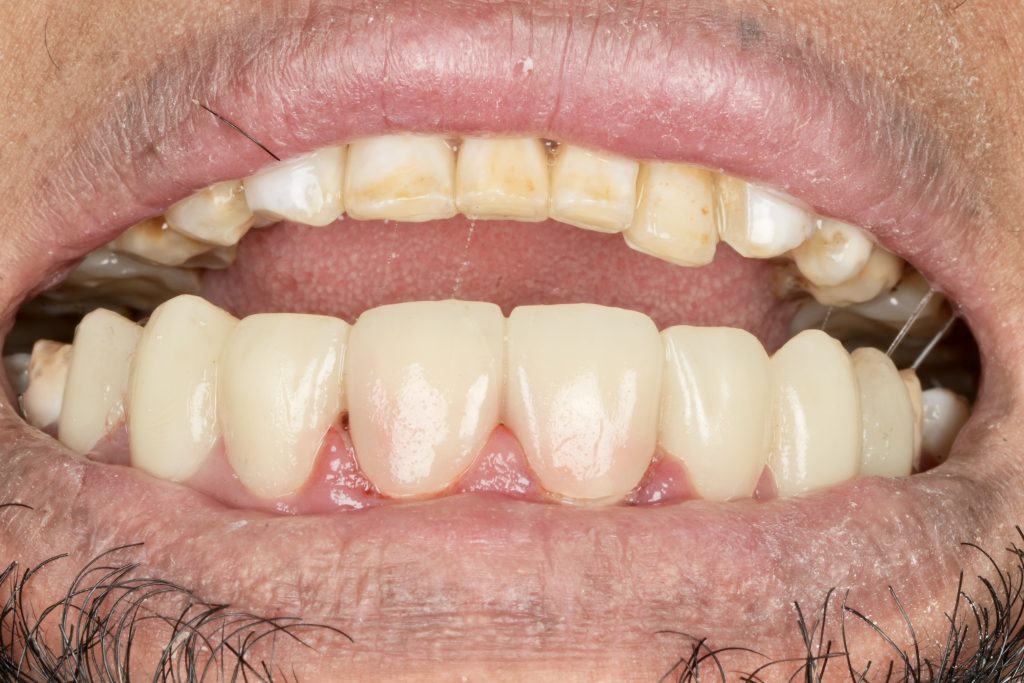

The patient sought esthetic improvement for uneven incisal edges, discolored anterior teeth, and disproportionate gingival display (Fig 1). A digital smile simulation and mock-up try-in were performed to assess tooth proportion, midline alignment, and incisal curvature. The plan prioritized enamel conservation and optical harmony.